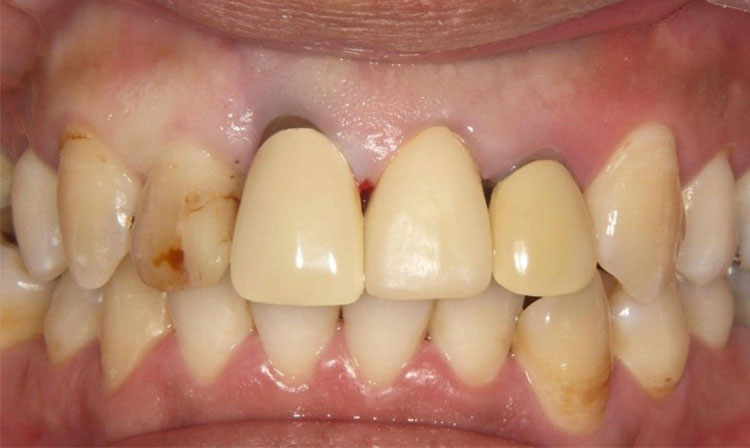

インプラント症例 Case3

Treatment cases

Before

After